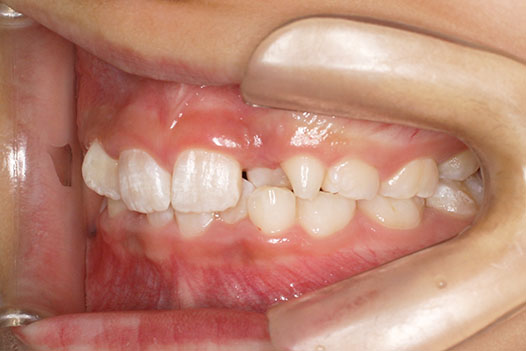

『前歯ががたついて生えてきた』 一般歯科から紹介の患者さんです。 上下4前歯に叢生がみられます。かみ合わせが深く、過蓋咬合。 上顎前歯は舌側傾斜。 永久歯の萌出スペースが上下とも5mmほど足りませんし、 おそらく、これから生えてくる犬歯は八重歯になる状況です。 治療方針としては、小児矯正で叢生(がたつき)を減らし、 永久歯列が生えてから、中学生ごろから本格矯正(マルチブラケット装置)を行います。 十分に側方拡大でスペースを確保し、更に、まだ生えていない永久歯の位置と方向が良ければ、きれいに生えそろうことにより、本格矯正での治療が必要ない場合もありますが頻度的には少ないです。 ある程度はきれいに生えてきても、左右の歯の高さの違いや、歯の回転、角度のズレが残る場合が多いからです。 その多少のがたつきが気にならないのでしたら、小児矯正で終了です。

小児矯正での早期治療で、側方拡大による十分なスペース確保をしていたことと、口唇の前突傾向がなかったことから、